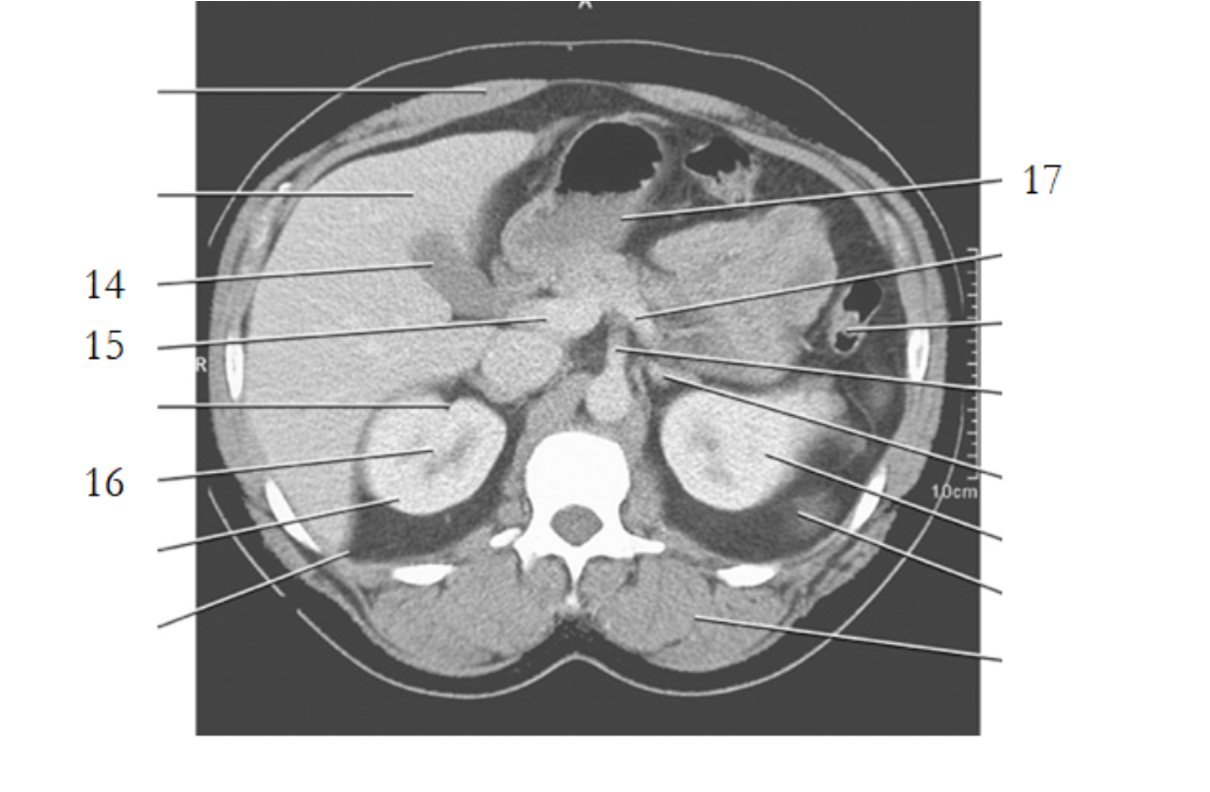

aorta

left renal vein

kidney

left renal artery

small bowel

large bowel

spleen